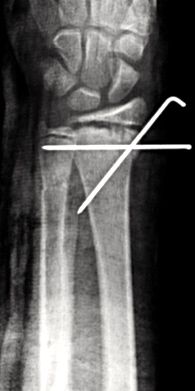

Las fracturas desplazadas o inestables precisarán de reducción cerrada o abierta en quirófano, asociado en algunos casos a osteosíntesis (Figura 10). Las fracturas localizadas en la unión metafiso-diafisaria distal son inestables y en muchos caos requieren tratamiento quirúrgico (Figura 11).

Figura 11: a, b-Fractura metafiso-diafisaria distal inestable. c, d-Control radiológico tras reducción donde se aprecia mala reducción. e, f-Síntesis mediante placa y tornillos.